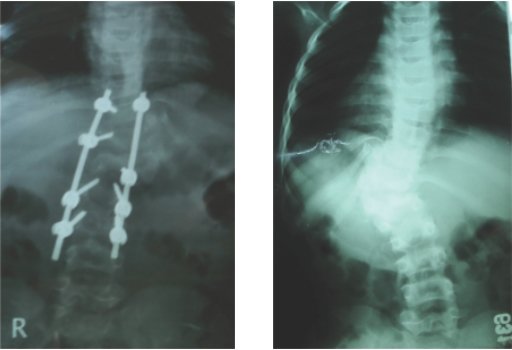

Double cord syndrome – DIASTOMATOMYELIA – is a very rare entity, wherein patient

is having congenital deformity of spine with separation of the spinal cord into

two halves by a bony or fibrous septum It is a great challenge to operate these

pts as , if something goes wrong, pt would become paraplegic for her life time.

Perticularly, in this case, as pt was only 9 years old and having congenital deformity

of the vertebrae, it was corrected simultaneously at Sola civil hospital - ahmedabad.

Hemivertebra Resection